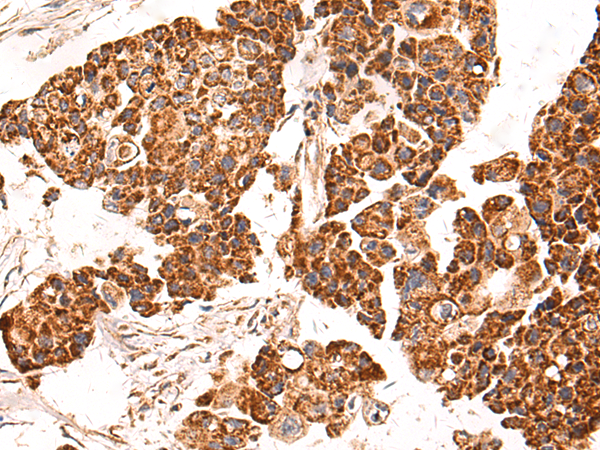

分类: 科研抗体货号: P10589别名: CAN19; S100L应用: WB,IHC反应种属: Human